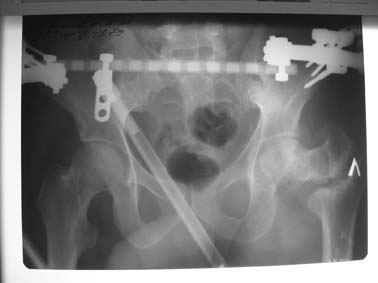

Возможно, пример (в приложении) поможет Вам определиться с выбором

тактики лечения (у нашего пациента, кроме тугого ложного сустава

вертельной области, сложная деформация н/3 бедренной кости; т.к. это

не имеет значения к обсуждаемой теме - оставил "за кадром"). Как Вы

видите, мы в данном случае не вводили чрескостные элементы в зону

установки имплантата. При отказе от наложения опоры на таз (кстати,

она не обязательно может быть громоздкая спицевая; арки со

стержнями-шурупами, введенными в крыло подвздошной вполне достаточно)

> Планируем внеочаговый остеосинтез спице-стержневым аппаратом,

> дистракция до восстановления длины бедра, вторым этапом остеосинтез

> стержнем Гамма. Есть надежда, что на дистракции пойдет сращение и у

> больного хватит терпения завершить лечение в аппарате.

> Компоновка аппарата: три стержня в центральный отломок на полукольце

> или сегменте, кольцо с тремя спицами в зоне мыщелков бедра, две из

> них с упорными площадками; по стержню в конец дистального отломка и

> диафиз. Нуждаемся в советах: